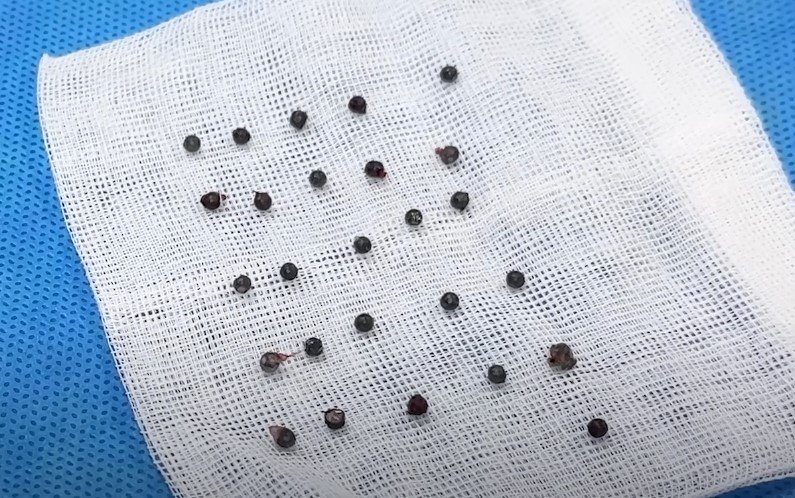

백구의 산탄총 파편 제거 수술은 3시간 넘게 진행됐다. 맨눈으로 탄알을 다 확인할 수 없어서 투시기를 이용해 수술을 진행했다.

안 원장은 “탄알을 한 번에 다 제거하기는 현실적으로 어려워 백구의 얼굴을 위주로 최대한 많이 제거하는 방향을 선택했다”며 총 26개의 파편을 제거했다고 설명했다.